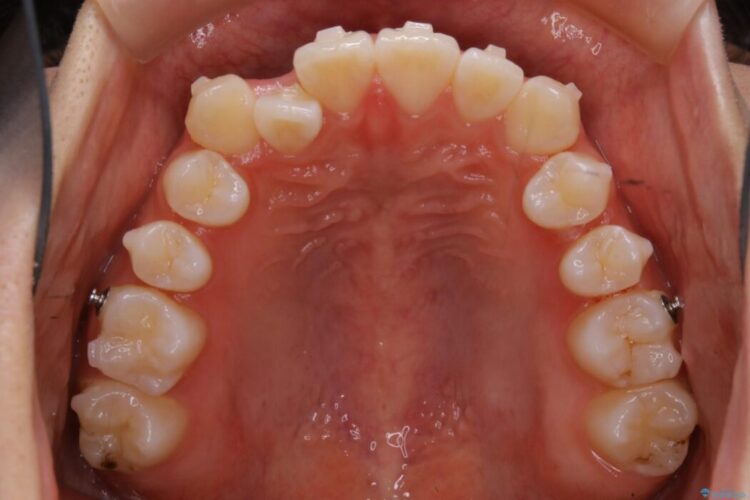

詳しく検査したところ、上顎の歯が舌側に倒れこんでしまっていることや歯列のガタガタなどにより口を閉じた時に上下の前歯の先端が接触してしまっていました。

更に深く噛もうと力を入れると、下顎が前方に突き出して前歯が当たらないように噛んでしまう機能性の反対咬合という診断となりました。

よってまずは上顎の歯列を整えることから始め、前歯同士の衝突を改善してから、噛みこむ位置を本来あるべき後方へと調整することとしました。

今回のケースでは非抜歯での治療を行っています。